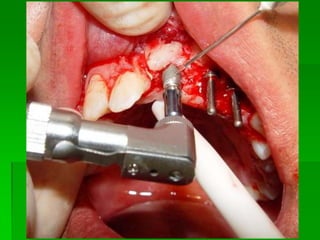

PRIMEIRA FASE CIRÚRGICAMOTOR PARA CIRURGIAPRIMEIRA FASE CIRÚRGICAKITS CIRÚRGICOSTipos de implante e indicações

Seqüência de Brocas

Avaliação Clínica no Momento da Instalação do ImplanteAparelhos especiais Osstell (mede por freqüência e ressonância)Avaliação Clínica (estabilidade)Torquímetro (mínimo 45 Newtons)Avaliação   radiográfica   ( durante   a instalação,  mede  a  distância   entre implantes e estruturas adjacentes)